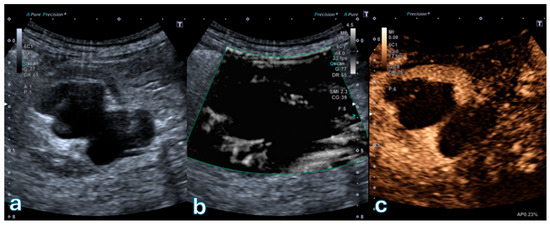

Figure 1

Background: The purpose of this study was to examine the relationship between qualitative characteristics and quantitative parameters from contrast-enhanced ultrasound (CEUS) and microvessel density (MVD) in hepatoblastoma (HB), as well as to investigate whether CEUS could be utilized as a non-invasive method for predicting HB progression. Methods: This retrospective analysis was carried out in one medical center and included 34 children with histopathologically confirmed HB. Both grayscale ultrasound and CEUS results were reviewed. Lesions were evaluated using time–intensity curve (TIC) analysis software to extract quantitative parameters. Postoperative tissue specimens were stained with CD34 immunohistochemistry, and MVD was quantified as the reference standard. Statistical analyses were conducted to assess the correlation between CEUS findings and MVD. Results: Lesions were separated into high (n = 21, 61.76%; MVD ≥ 41) and low (n = 13, 38.24%; MVD < 41) MVD groups, using the median microvessel density of 41 vessels per high-power field (HPF) as the cutoff. High MVD lesions exhibited a significantly higher incidence of penetrating vessels compared with low MVD lesions (p < 0.05). Elevated MVD levels were significantly associated with increased Adler-grade blood flow (p < 0.05). Both TIC-derived and relative quantitative parameters exhibited significant intergroup differences. Among the relative parameters, the relative wash-out rate (rWoR) was significantly higher in the low MVD group (p < 0.05). Moreover, the Receiver Operating Characteristic (ROC) curve analysis indicated that an rWoR threshold of ≥1.36 could serve as a predictor for low MVD, resulting in 76.9% sensitivity and 81.0% specificity (AUC = 0.802; 95% CI: 0.634–0.970; p = 0.003). Conclusions: CEUS revealed an association with MVD, supporting its potential as a non-invasive tool to characterize tumor vascularity. Full article